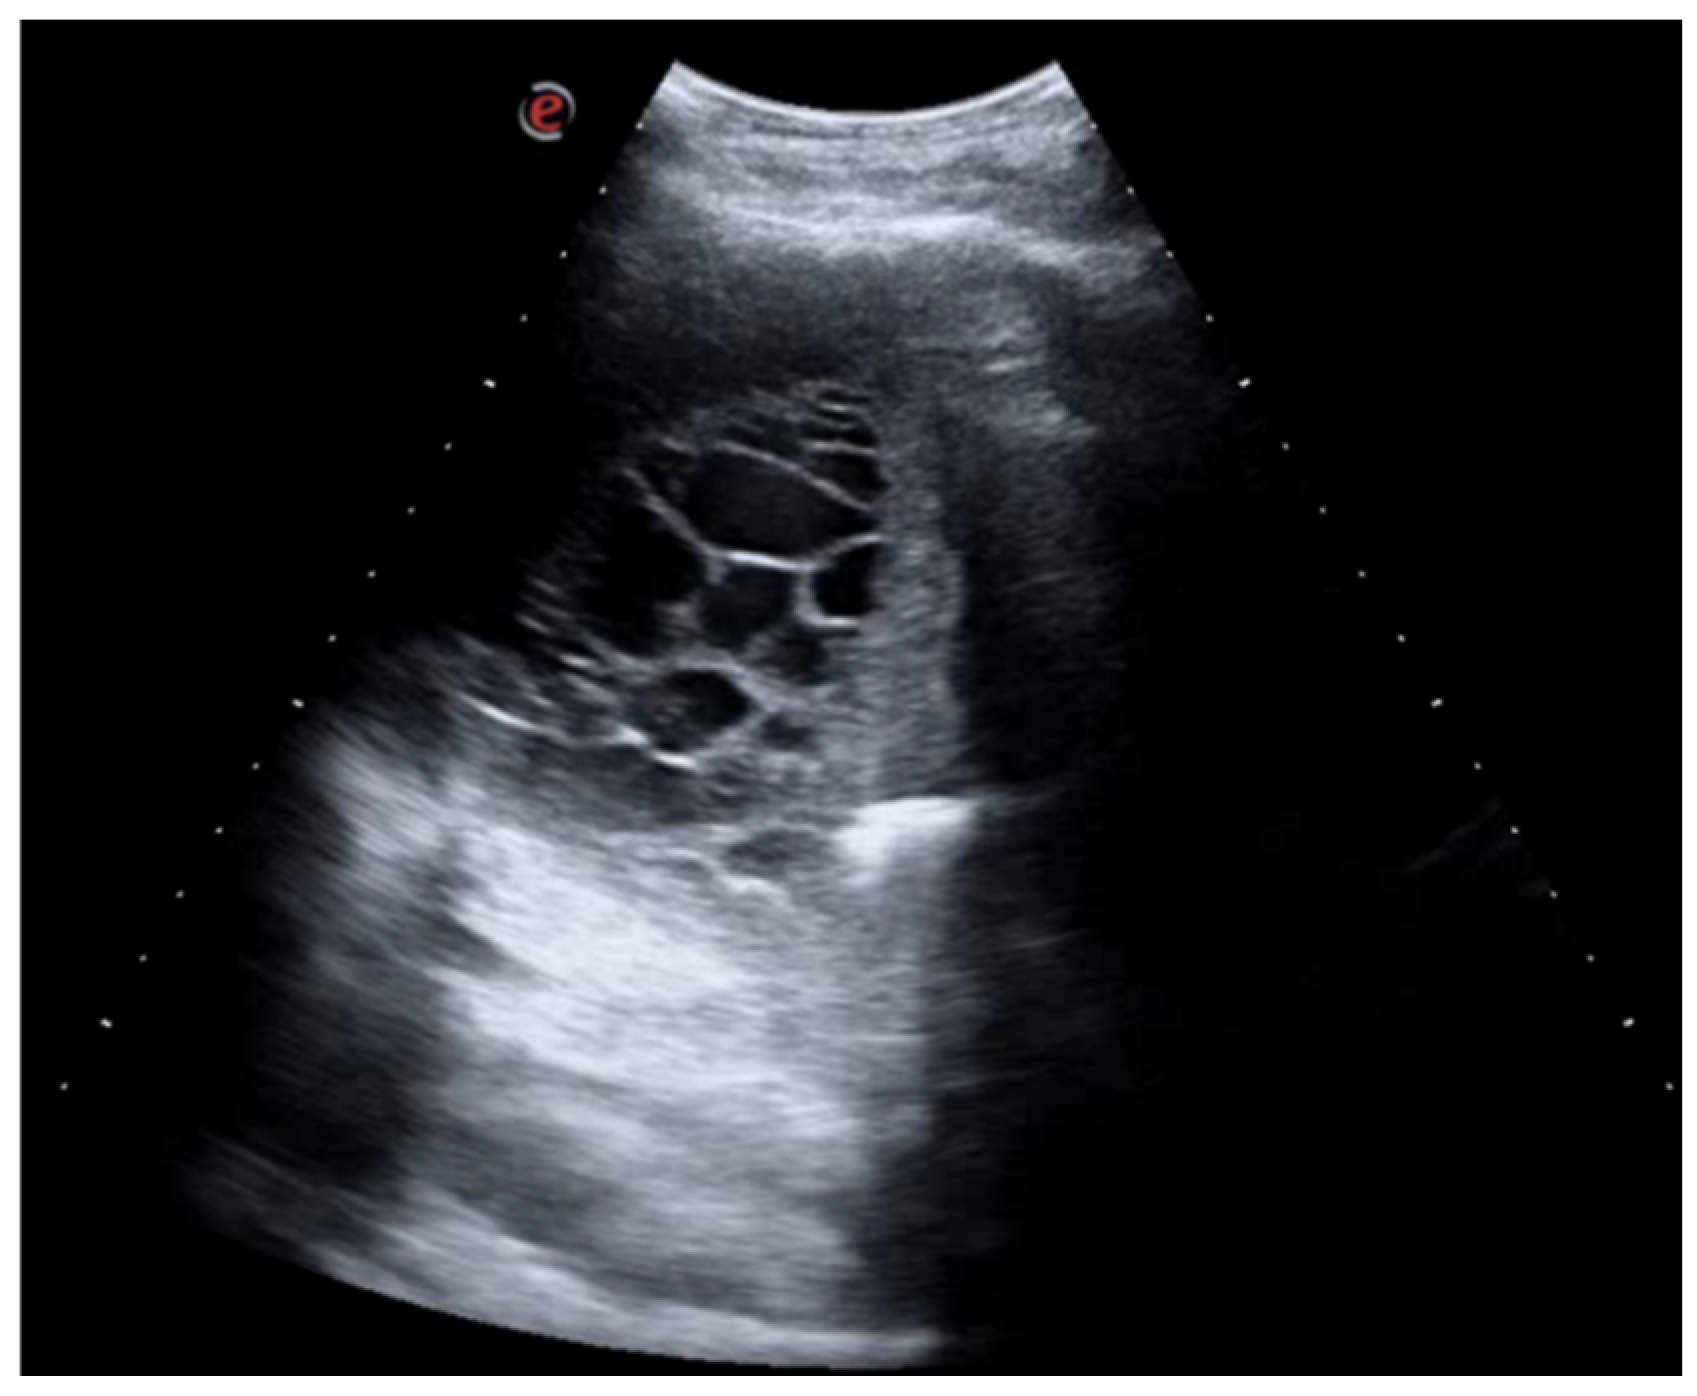

A chest US showed multiloculated PEff with septations of different thicknesses (Figure 9). A 12 Fr chest tube was placed, and 1000 mL of turbid fluid were drained. Samples were collected for microbiological and physicochemical analysis. Irrigation of the pleural cavity with 200,000 IU of urokinase in 50 mL of saline solution was performed under US guidance (Video 1). This was followed by the closure of the chest drain for 3 h, and then it was reopened. Further irrigation with 100,000 IU was performed 24 h later. Empiric antibiotic therapy with 500 mg azithromycin (q24h) for 6 days and 4.5 g piperacillin/tazobactam (q8h) for 2 weeks was administered. A chemical analysis of the pleural fluid revealed exudate. The microbiological study was negative.

Figure 9. Chest ultrasound at admission showing multiloculated pleural effusion.